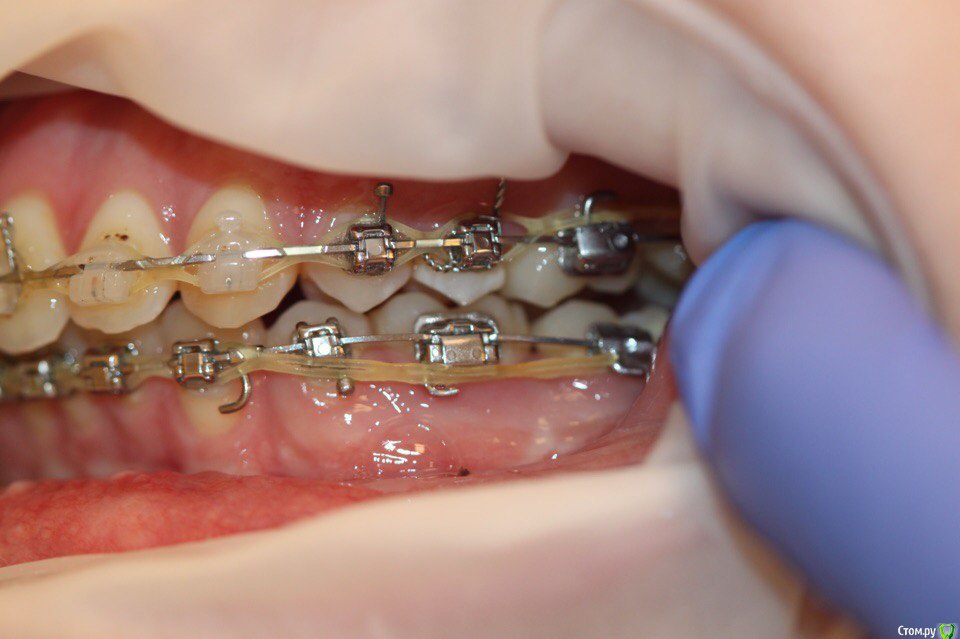

annurka Опубликовано 12 сентября, 2017 Поделиться Опубликовано 12 сентября, 2017 (изменено) здравствуйте! 24 года, дисфункция ВНЧС, дистальный прикус (1,4см), ортодонтическое лечение начато с ношения каппы для разгрузки сустава (привыкла подтягивать НЧ к верхней) в 2012 году. проведено лечение: удаление всех 8к (непрорезавшиеся), расширение ВЧ (аппарат дерихсвайлера), выравнивание зубных рядов, сепарация нижних резцов (резцы были наклонены), места не хватило - удаление 2 нижних 4к, выравнивание кривой шпее, двухчелюстная остеотомия; выравнивание окклюзионных контактов (резиновые тяги) проблема: между верхними и нижними резцами расстояние 5мм к трг (внизу фото) есть расшифровка.все идет к снятию брекетов, и с эстетической точки зрения меня все устраивает. но не до конца устраивает в функциональном плане (я не могу пропихнуть палец между зубными рядами, как раньше, но все также подтягиваю челюсть кпереди когда ем, говорю)стараюсь контролировать это, но даже улыбнуться не могу не подтянув - иначе у меня некрасиво вырисовывается подбородок, неправильно произношу звуки при разговоре.сразу после остеотомии состыковка резцов была ок - нижние зубы были за верхними, но мы с ортодонтом занялись состыковкой и других зубов (которые тогда не соприкасались), и когда добились контактов жующих сторон, разошлись резцы.UPD: и еще есть черные треугольники на НЧ - с ними тоже очень хочется разобраться лечащий ортодонт говорит, что это в целом норма, с учетом моего случая. и возможно это так, но я очень хочу послушать еще мнений, возможно стоит удалить 2 зуба наверху, чтобы верхняя челюсть подошла по размер нижней? [боюсь что простой сепарации может не хватить и как в случае с нижними резцами придется и сепарацию делать, и удалять зубы.] может быть еще есть другой способ добиться нормального прикуса, без "нюансов"?изначально я пошла на все это лечение, чтобы остановить разрушение сустава (однажды проснулась и не смогла рот даже открыть, еще до лечения), полагала, что брекеты и члх исправят если не ситуацию, то причину, но я все еще двигаю НЧ вперед к ВЧ. с остеотомии прошел почти год (поэтому на изменение картины эластиками я уже не надеюсь), брекеты ношу почти 4 года. заранее всем спасибо за отклик! Изменено 12 сентября, 2017 пользователем annurka 1 Ссылка на комментарий

annurka Опубликовано 13 сентября, 2017 Автор Поделиться Опубликовано 13 сентября, 2017 (изменено) А До лечения есть ТРГ посмотреть? И фото какие-нибудь?есть трг сверху - сразу после остеотомии, снизу - через полгода после (когда резцы отошли друг от друга на 5мм) до лечения вообще точно делал ортодонт (снимки, слепки, фото), если в клинике это сохранили, я смогу сфотографировать. далее фото в процессе лечения - 4ки нижние еще не удалены, один хирург был готов так оперировать, другой сказал, что наклон нижних резцов неправильный и нужно как и было запланировано удалить 4ки, сепарации недостаточно.челюсть расслаблена как есть: НЧ подвинута к ВЧ для наглядности: есть фото слепков того периода, но форум ругается на слишком большой размер. если нужно - уменьшу залью) Изменено 13 сентября, 2017 пользователем annurka 1 Ссылка на комментарий

annurka Опубликовано 13 сентября, 2017 Автор Поделиться Опубликовано 13 сентября, 2017 (изменено) вот трг до начала лечения, фото к сожалению нет, если только из жизни) расшифровка трг ДО (где выделено синей ручкой) и недавнее Конечно контакты не идеальны, но если удалить 4ки наверху нижняя треть лица будет иметь довольно вогнутый вид спасибо за комментарий! а если сделать сепарацию резцов, тогда получится избежать вогнутости профиля? С ДВНЧС у вас сейчас проблемы остались? Можно рассмотреть совместно с врачом аппараты для выдвижения нижней челюсти,если тяги не справляются не было до недавнего времени - сейчас иногда болит в области сустава слева (видимо потому что контакты справа уже есть, а слева в процессе, поэтому нагрузка на челюсть неравномерная ?). до операции (но после начала лечения брекетами) сустав не беспокоил, надеюсь это просто период реабилитации.насчет аппаратов по выдвижению НЧ - спасибо, передам ортодонту.с6нимки к сожалению выполнены в разных клиниках, но мне казалось что если судить по трг через полгода, то НЧ там же, где была закреплена титановыми пластинами сразу после остеотомии (но проблема с резцами тогда уже возникла)... или мне так только кажется и произошел рецидив? думаете ее можно еще двинуть вперед? Изменено 13 сентября, 2017 пользователем annurka Ссылка на комментарий